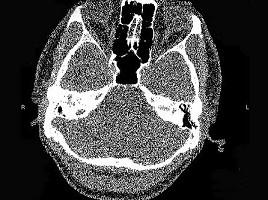

男,23岁,右耳流脓十余年,右外耳道流脓,鼓膜穿孔,CT检查如图,最可能诊断为 ( )

• A.中耳癌

• B.嗜酸性肉芽肿

• C.(海绵化期)耳硬化症

• D.中耳乳突结核

• E.慢性中耳乳突炎

答案: E